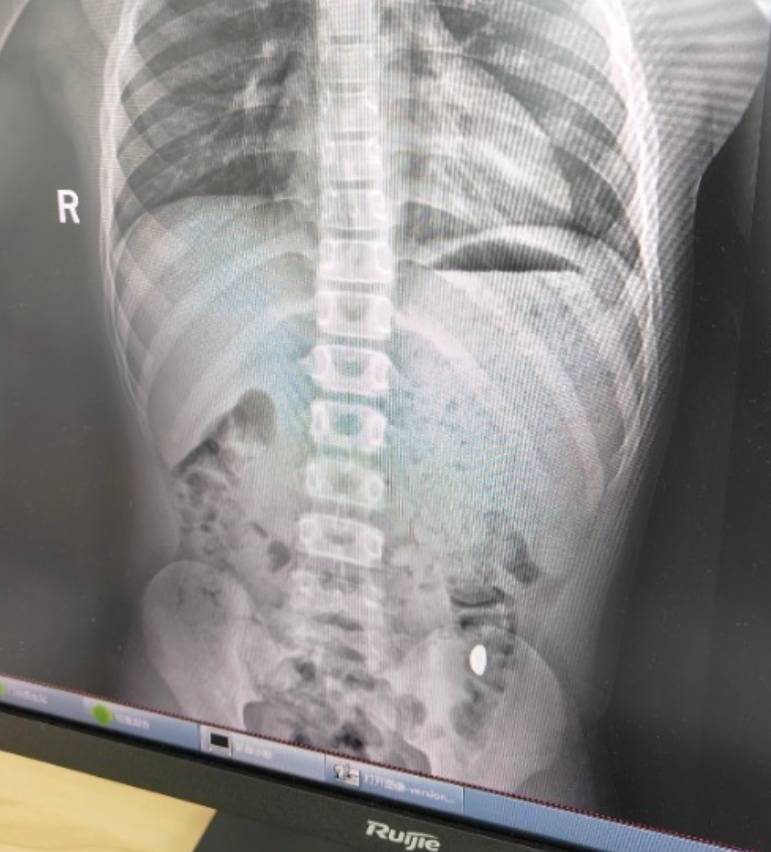

右下加亮点为金豆币率兑换。